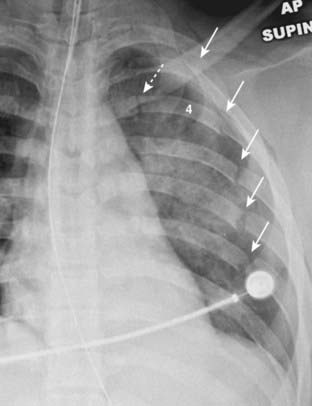

image

Figure 17-4 Pulmonary lacerations, conventional radiograph, and CT.

Lacerations are sometimes masked, at least for the first few days, by the airspace disease in a surrounding pulmonary contusion. A, If they are completely filled with blood, they will appear as an ovoid mass (dotted white arrow). B, If they are partially filled with blood and partially filled with air, they may contain a visible air-fluid level (solid black arrow). Unlike the neighboring pulmonary contusion (solid white arrow), pulmonary lacerations, especially if they are blood filled, may take weeks or months to completely clear. The top of the left hemidiaphragm (D) is seen in this image.